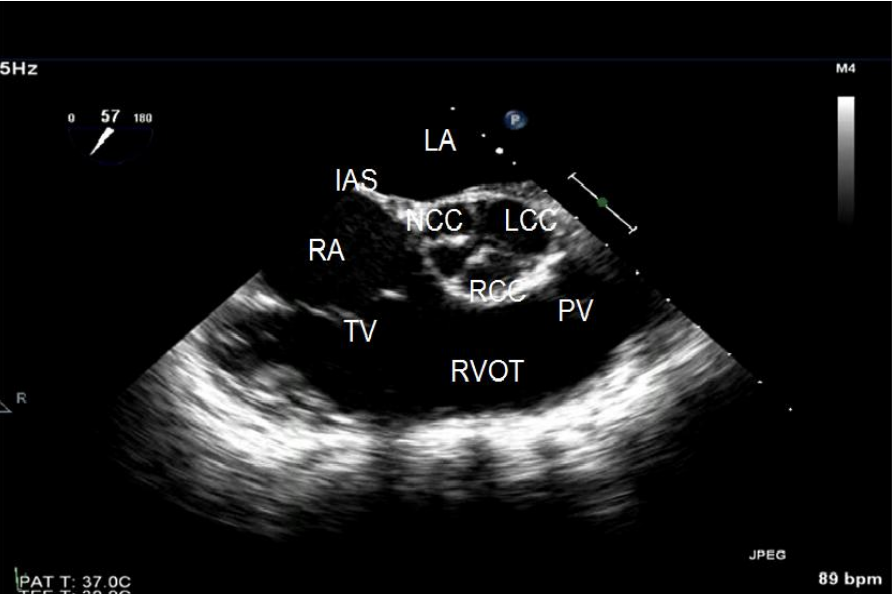

In the mid-esophageal TEE short axis view of the aortic valve, which cusp is:

***in normal trileaflet valves

What view is best to aid in TEE guided transseptal puncture (either anteriorly or posteriorly)?

Short-axis view at the level of the aortic valve (at the level of the aortic root)